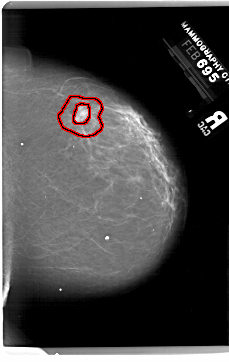

A_1999_1.RIGHT_MLO

RIGHT_MLO LINES 6196 PIXELS_PER_LINE 4306 BITS_PER_PIXEL 12 RESOLUTION 43.5 OVERLAY

FILE: A_1999_1.RIGHT_MLO.OVERLAY

TOTAL_ABNORMALITIES 1

ABNORMALITY 1

LESION_TYPE MASS SHAPE IRREGULAR MARGINS SPICULATED

ASSESSMENT 5

SUBTLETY 3

PATHOLOGY MALIGNANT

TOTAL_OUTLINES 2

BOUNDARY

CORE